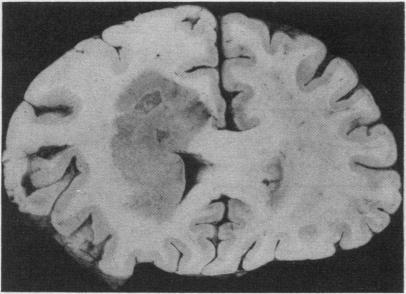

Seventy cerebral lymphomas from 37 men and 33 women were reviewed and reclassified using the modified Kiel classification. Fifty two of the patients were over the age of 50 years (age range 23-85 years). Only two patients were known to be immune deficient--one case of AIDS and one renal transplant recipient. Necropsies only were performed on 31 cases, biopsies only in 23 cases, and both biopsies and necropsies in 16 cases. Systemic tumour was found in 16 of 47 necropsy cases. All the tumours available for review were classic diffuse non-Hodgkin's lymphomas. Where immunocytological studies were positive, the tumour cells were of B cell origin. None was of T cell origin, although reactive T cells in the tumours were frequently identified. It is concluded from this and other studies that the incidence of intrinsic cerebral lymphomas is increasing.

我们使用改良的基尔分类法对来自37名男性和33名女性的70例脑淋巴瘤进行了回顾和重新分类。其中52例患者年龄超过50岁(年龄范围为23 - 85岁)。已知仅2例患者存在免疫缺陷——1例艾滋病患者和1例肾移植受者。仅对31例进行了尸检,仅对23例进行了活检,16例同时进行了活检和尸检。在47例尸检病例中有16例发现存在系统性肿瘤。所有可供回顾的肿瘤均为经典的弥漫性非霍奇金淋巴瘤。免疫细胞研究呈阳性时,肿瘤细胞起源于B细胞。尽管肿瘤中经常可识别出反应性T细胞,但无一例起源于T细胞。基于此项研究及其他研究得出结论,原发性脑淋巴瘤的发病率正在上升。